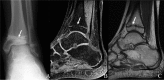

Context: As the intensity of youth participation in athletic activities continues to rise, the number of overuse injuries has also increased. A subset of overuse injuries involves the physis, which is extremely susceptible to injury. This paper aims to review the utility of the various imaging modalities in the diagnosis and management of physeal injuries in the skeletally immature population.

Results: Three major imaging modalities (radiographs, computed tomography, and magnetic resonance imaging) complement each other in the evaluation of pediatric patients with overuse injuries. However, magnetic resonance imaging is the only modality that offers direct visualization of the physis, and it also offers the best soft tissue contrast for evaluating the other periarticular structures for concomitant injury.

Conclusion: Imaging has an important role in the diagnosis of physeal injuries, and the information it provides has a tremendous impact on the subsequent management of these patients.